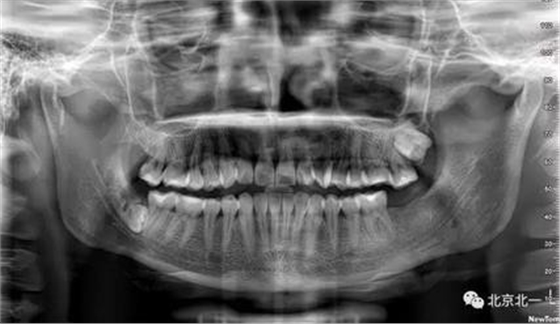

病例資料:一般情況,患者女性,28歲, 主訴:要求拔右側(cè)下頜智齒,檢查:右側(cè)下頜第三磨牙未見萌出, 拍片如圖。

圖一:CBCT顯示右側(cè)下頜水平骨埋伏牙,牙冠距離下牙槽神經(jīng)管接近。